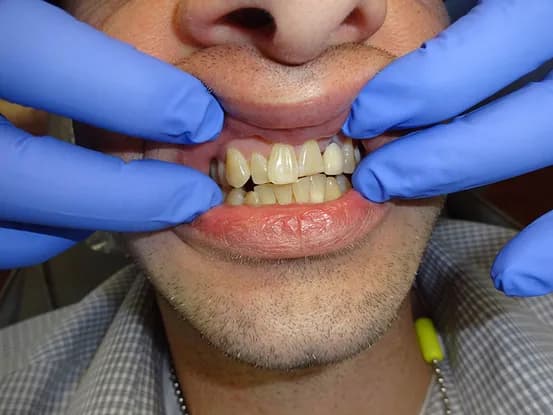

Case 9

43 year old male with discolored and malaligned teeth. Patient does not want orthodontics and only wanted upper teeth done. 6 units of porcelain crowns performed to improve smile line